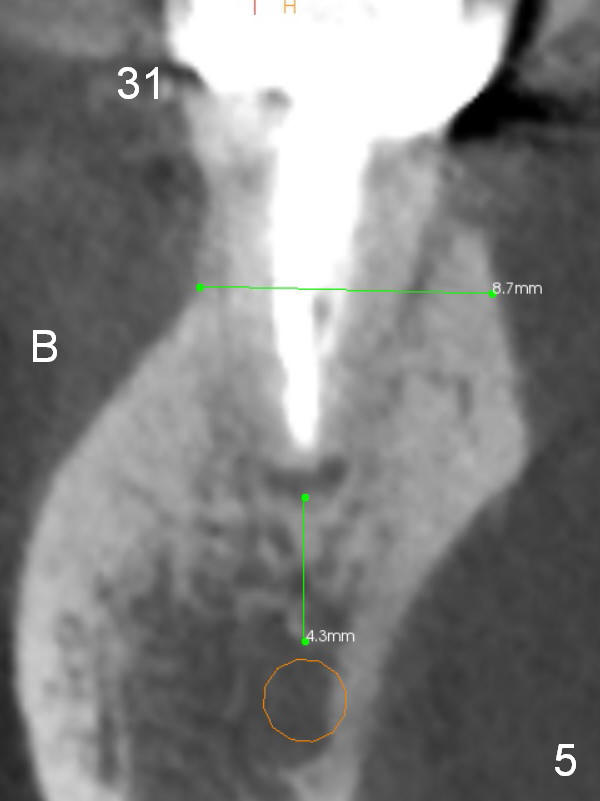

A 71-year-old man requests restoration at #18-20 (Fig.1). Placing implants at the narrow ridge of the sites of #18 and 19 is quite challenging (Fig.3,4), as compared that at #31 (Fig.5). Since the bone density at the crest is high (1200-1500 u), use a surgical high speed fissure bur for sectioning the crest, followed by BEB at 11 mm. It appears safer to place 1-piece implant (Fig.3) than 2-piece one (Fig.4). Since the total mesiodistal distance for #18-20 is 18 mm, splinting the three-units should be a sound treatment option.